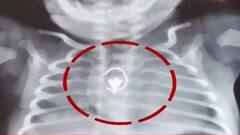

SSKM: ২৮ দিনের শিশুর শ্বাসনালী থেকে বের করা হল নাকছাবি, জটিল অস্ত্রোপচার এসএসকেএমে